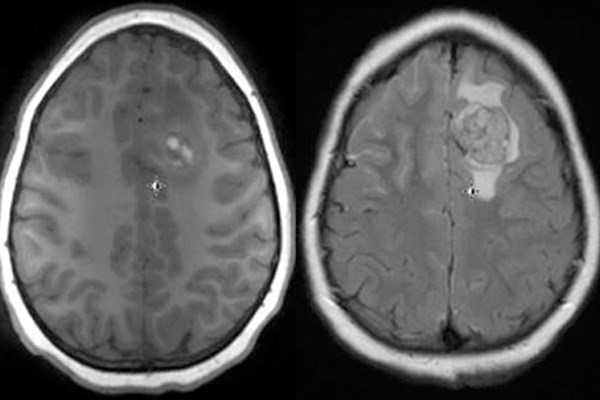

Emergent MRI scans of the brain and spine were obtained, revealing multiple linear and nodular lesions with extensive leptomeningeal enhancement with diffuse craniospinal melanomatosis suggestive of NCM.

MRI of the brain shows nodular area with hyperintense (T1 signal) in the left frontal lobe with surrounding edema consistent with metastatic lesion and significant diffuse leptomeningeal enhancement.